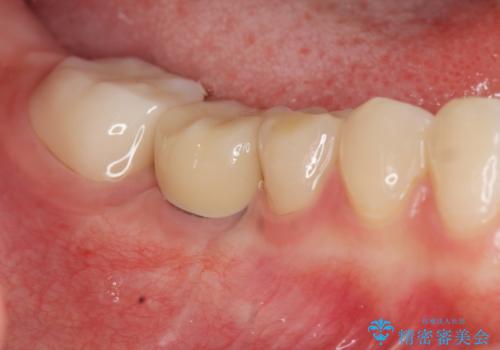

- 70万円(仮歯・ジルコニアクラウン×3 ストローマンインプラント・アバットメント)費用は治療当時の料金となります

歯を失ってからの時間が経過し骨が吸収してしまっていても、造骨を行うことで予知性の高いインプラント治療を行うことができます。